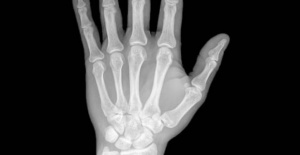

Reumatoid artrit orsakar inflammation i leder och vävnader, vilket är det som gör normala rotationsrörelser så svåra. Det är en autoimmun sjukdom, vilket innebär att den uppstår när individens immunförsvar angriper denne av misstag.

Nästan alla människor som lider av denna sjukdom har erfarenhet av intensiv smärta i lederna som är mycket starkare tidigt på morgonen; de upplever ofta intensiv värme, rodnad eller deformering av lederna, liksom att händer och fötter ofta somnar.